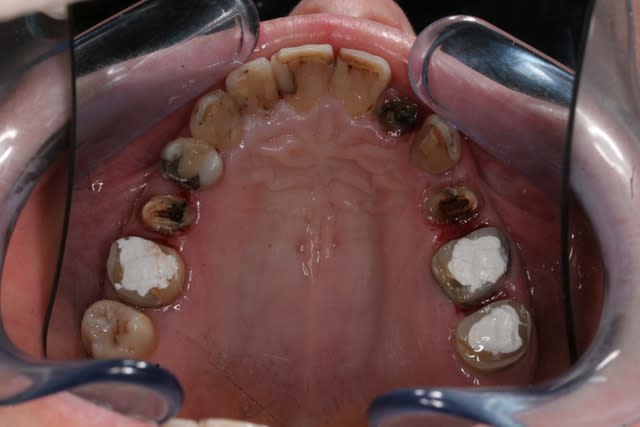

Récemment Céramik râlé, parce qu'il n'y avait pas de nouveau cas (esthétique je crois) à se mettre sous la dent. Je me jettes à l'eau avec ce dernier cas posé ce vendredi (y'a pas plus frais), une larme à l'oeil parce qu'il s'agit aussi du dernier gros cas dans mon cabinet que je quitte cette semaine pour rejoindre ma belle et nos p'tits bouts loin la bas dans le sud.

La patiente a un sourire très médiocre avec migration de plus en plus marqué du bloc incisivocanin sup. Comment l'aidez vous?

Cas de ré-hab globale comme j'aime bien

Tous est à refaire dans cette bouche, amalgames horibles, couronne brisée, etc

Céramiques haut et bas, au complet

Voila la suite pour le maxillaire, le wax est fait sur arti en fonction de l'OIM obtenue après ortho. seule la 27 restera intacte.

Préparation des molaires pour permettre des RTE sous digue à travers les provisoires, retrait des anciennes couronnes et ancrages sur les 12, 15 et 25 endo satisfaisantes (couronnes ayant plus de 30 ans pour certaines!!!.

Tailles parallèles pour zircone 13 à 23 seront solidarisées pour éviter une migration post ortho.

Gingivectomie légère à la fraise à biseau pour harmoniser les collets, mais l'ortho a permis d'énormément faciliter ce travail.